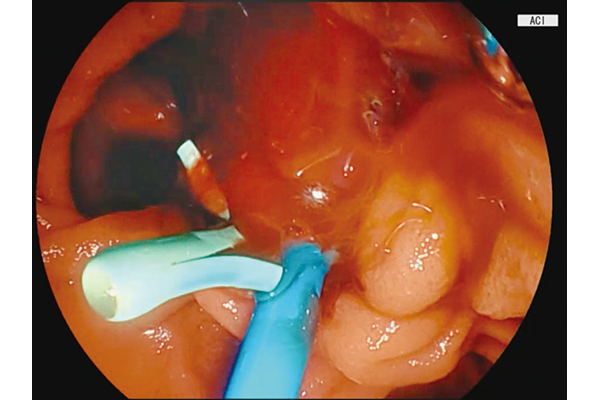

BLI,LCI and ACI technologies are incorporated.

- * ACI technology is available with the combination of EP-8000 only